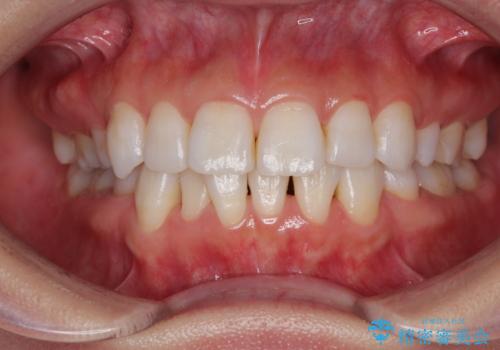

- 上下前歯の後戻りを気にして来院された患者様です。

インビザラインでの治療を希望されていて、デコボコの程度が中等度であり、安価なパッケージにて対応可能と判断されたため、インビザライン・モデレートを用いて矯正治療を行うこととしました。